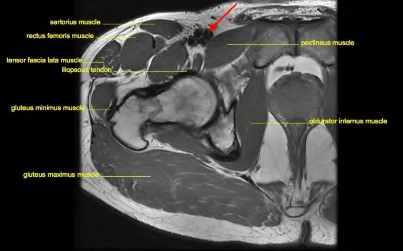

A surgeon is performing a total hip arthroplasty via the direct anterior (Smith-Petersen) approach. This approach exploits the internervous plane between which two muscle groups?

Explanation

A direct anterior approach to the hip utilizes an internervous and intermuscular plane. Which of the following accurately describes this superficial interval?